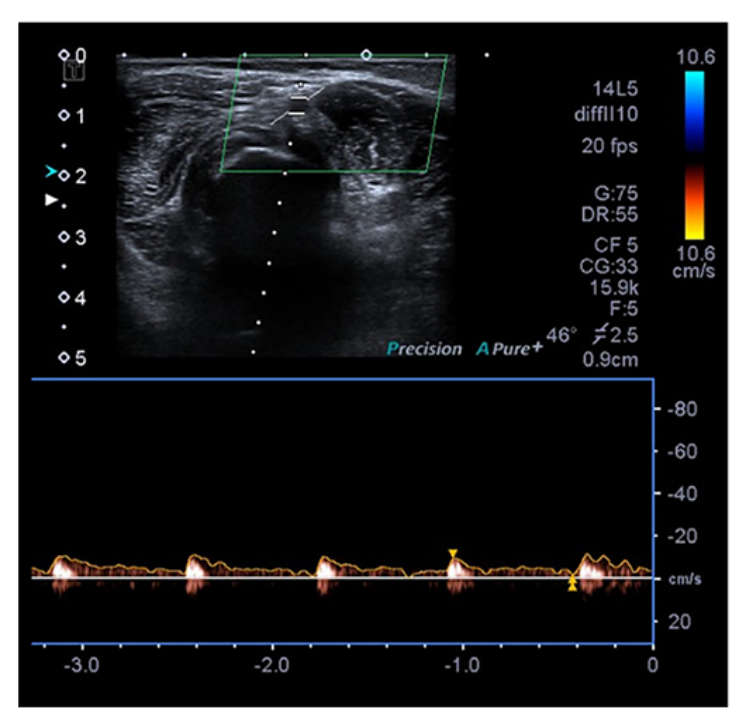

超声对早期RAO的评估

早期桡动脉闭塞(RAO)被定义为在24小时内发生的桡动脉闭塞。在移除TR-Bands后进行24小时的超声检查。如果通过多普勒超声无法检查到桡动脉血流,则视为早期桡动脉闭塞,并注意患者是否有前臂疼痛或血肿(见图3、图4)。

图4:多普勒超声可以检出桡动脉血流,考虑为非RAO